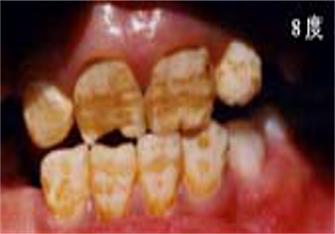

儿童牙齿发育过程中摄入过量的氟会引起氟斑牙:

可疑:上中切齿唇面有白色薄雾状或条状白色横纹

极轻度:上中切齿唇面有条状白色斑纹,占牙面1/4以下。

轻度:白色条纹或斑块,占牙面1/2以下,可出现浅棕色着色。

中度:上中切齿或全口牙整个牙面出现白垩,失去光泽,有明显着色。有的出现小点状凹坑。

重度:全口牙面呈白垩,出现散在坑凹状缺损或融合成片状缺损,有较重的着色。